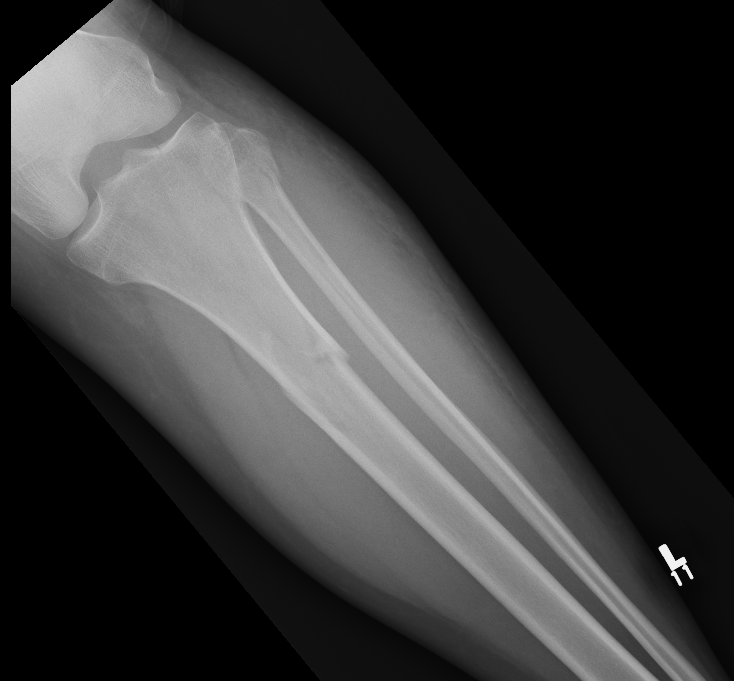

Metaphysical / extra-articular

Deformity

- abductors/hamstrings (pes) = varus of proximal fragment = valgus of fracture

- patella tendon = extension of proximal fragment = procurvatum of fracture

Characteristic valgus deformity with extension of the proximal fragment